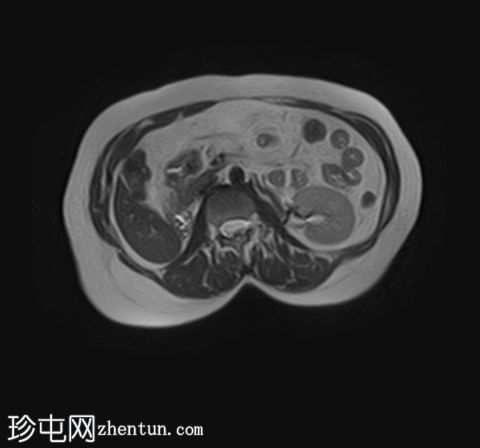

MRI

轴位T1加权像

(同相/反相)

轴位

T1加权像

脂肪抑制像

左侧肾上腺可见一边界清晰的病灶,大小约为3.0 × 2.4 × 2.0 cm。

化学位移成像显示,反相图像的信号强度较同相图像明显降低,与细胞内脂质含量相符。

右肾先天性缺失。左肾轻度肥大,信号强度正常。

肾上腺腺瘤的典型表现,反相成像可见明显的信号丢失。